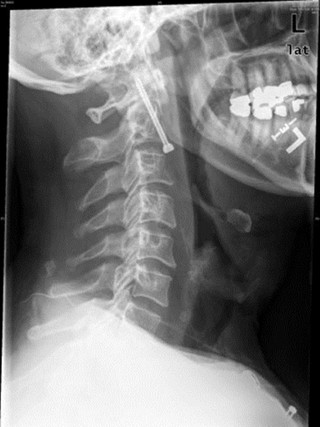

Ακτινογραφίες που σοκάρουν!

Όταν η επιστήμη σηκώνει τα χέρια ψηλά